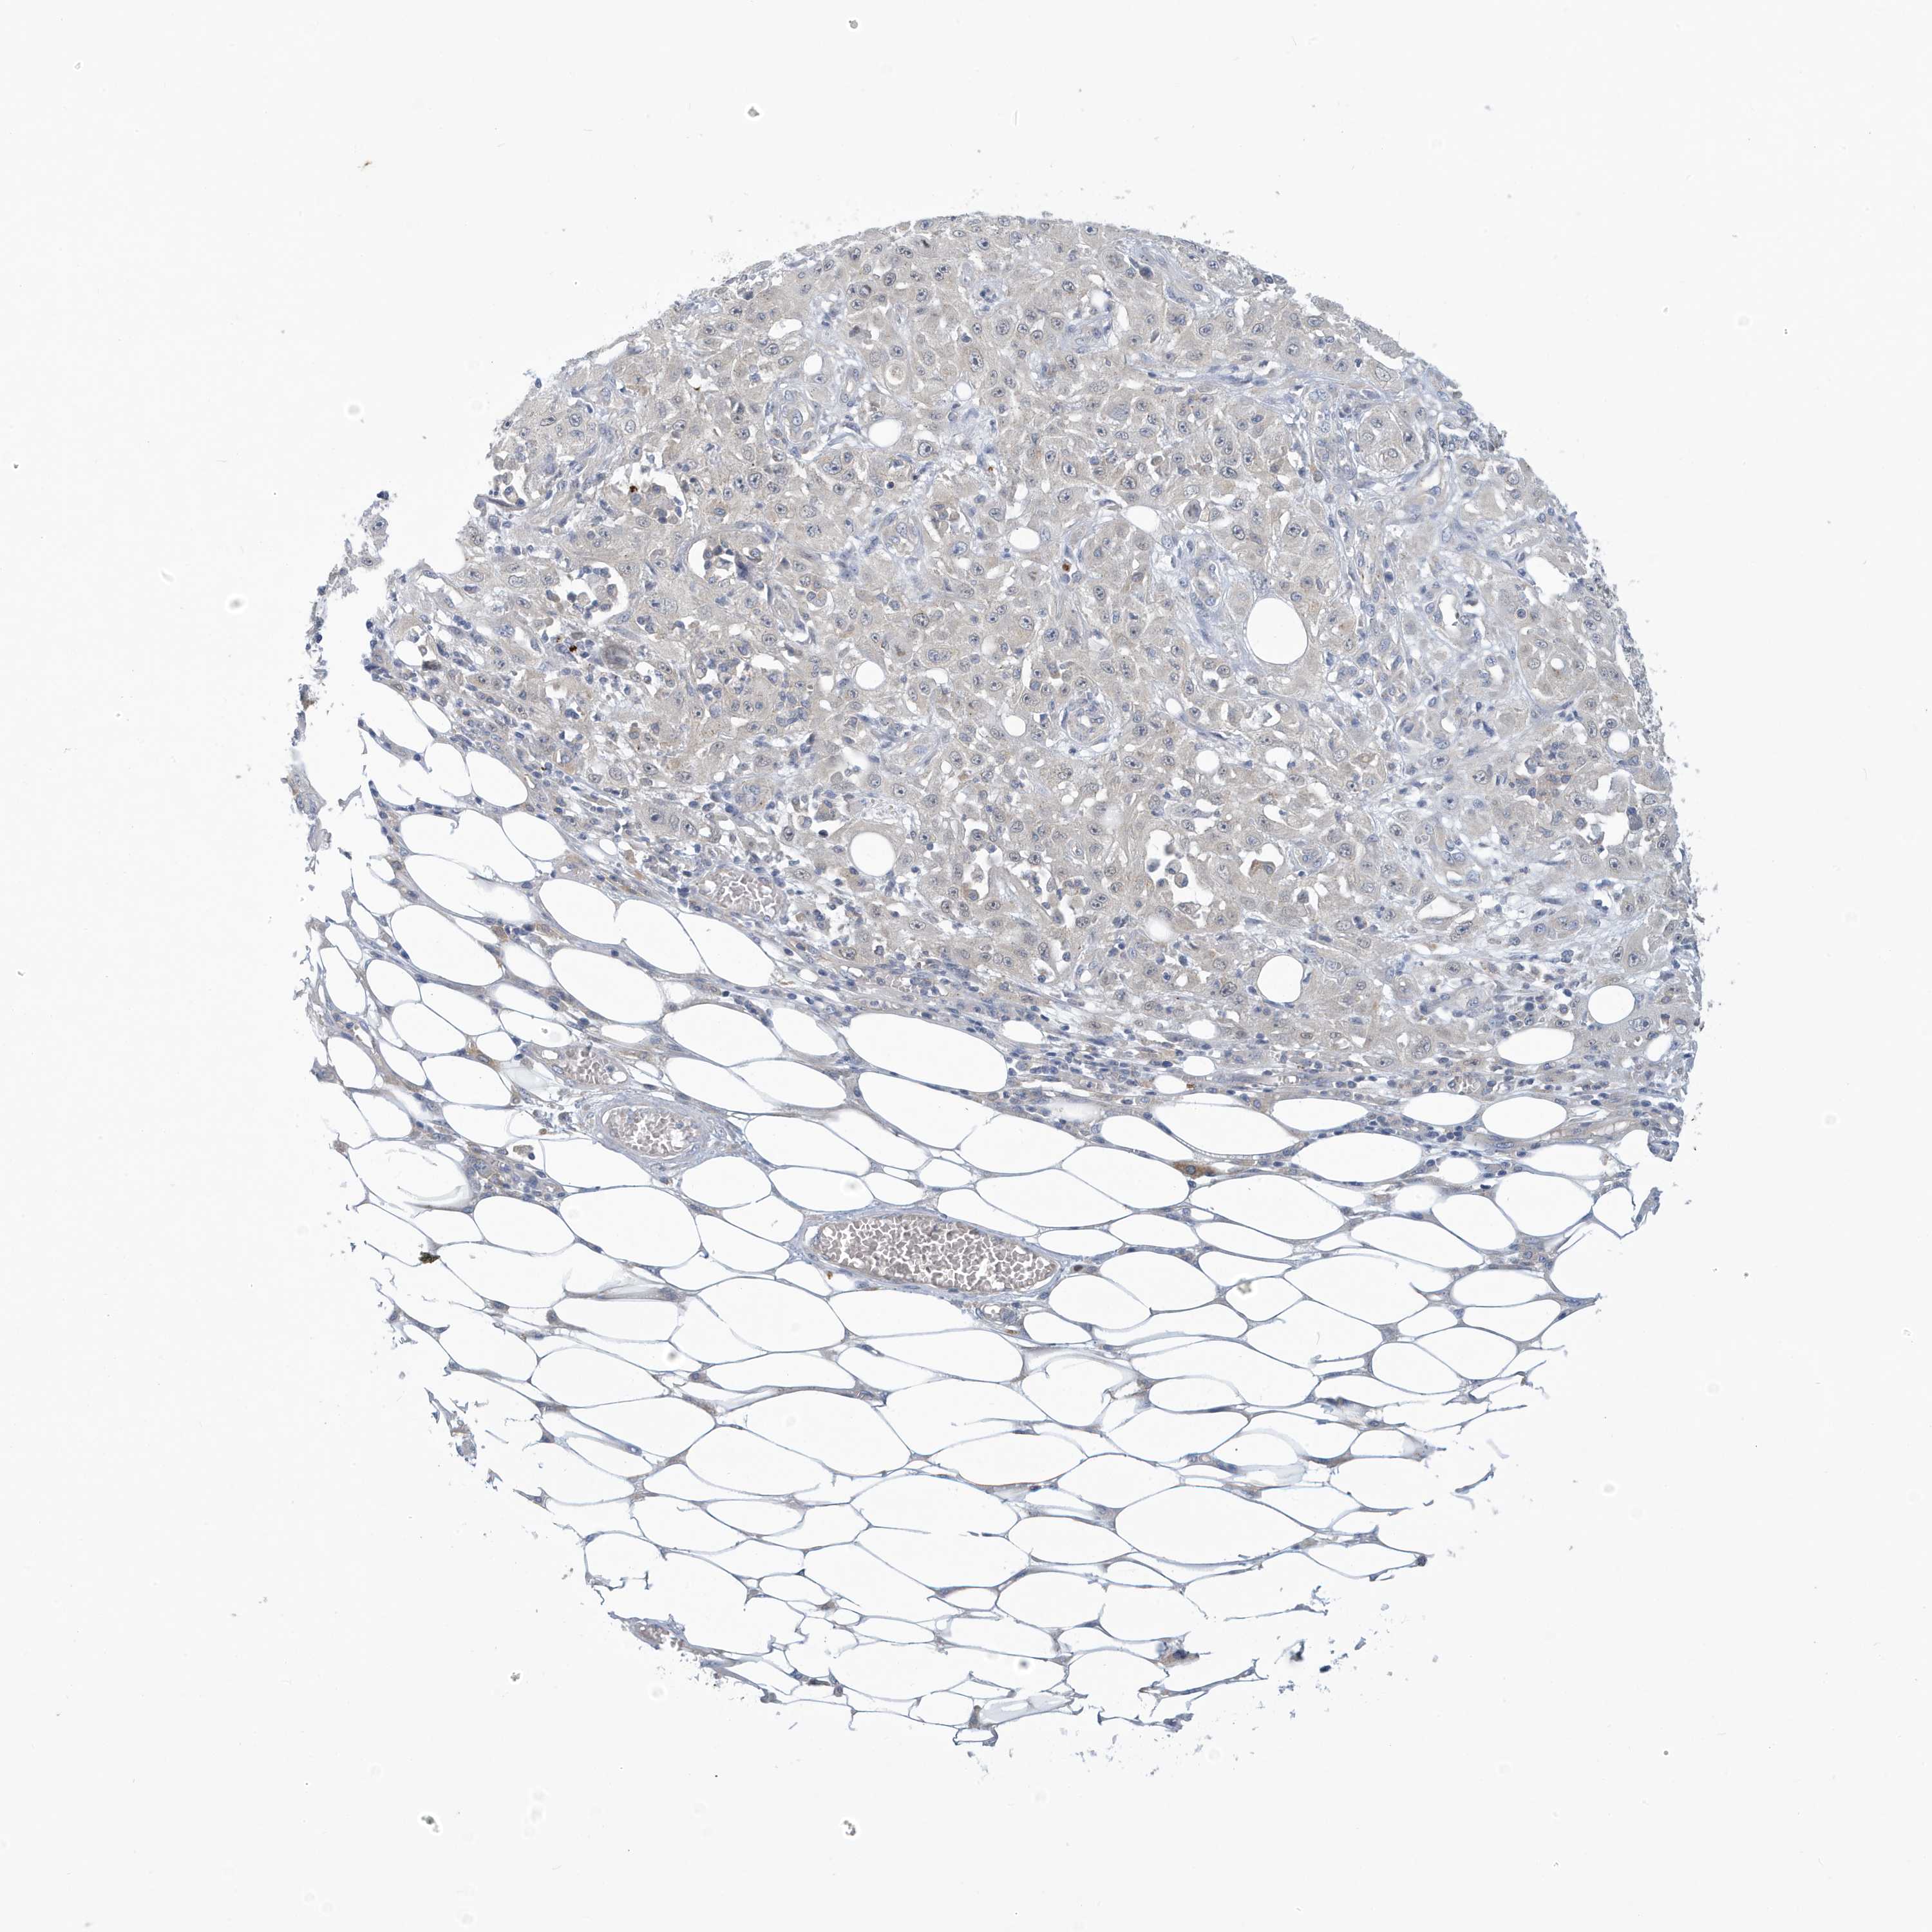

Basal cell and squamous cell cancer

SKIN CANCER - Protein expressioni

A mouse-over function shows sample information and annotation data. Click on an image to view it in a full screen mode. Samples can be filtered based on level of antibody staining by selecting one or several of the following categories: high, medium, low and not detected. The assay and annotation is described here.

Each image is clickable and will lead to virtual microscopy that enables deeper exploration of all samples and also displays staining intensity scores, fraction scores and subcellular localization as well as patient and tissue information for each sample.

Antibody HPA030968

Staining

High

Medium

Low

Not detected

Intensity

Strong

Moderate

Weak

Negative

Quantity

>75%

75%-25%

<25%

None

Location

Nuclear

Cytoplasmic/membranous

Cytoplasmic/membranous,nuclear

Squamous cell carcinoma, NOS